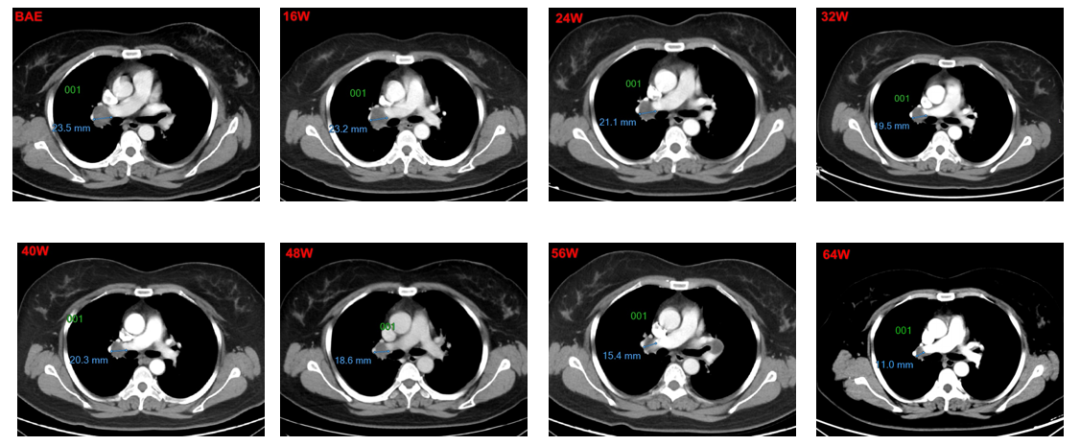

2015-06-18,接受肝左叶切除术,切缘阴性,术后恢复良好。2016.11,复查CT提示双肺结节增大,考虑双肺转移。2016-11-28,患者首次接受多纳非尼治疗(0.2g,每日两次口服),治疗初期,靶病灶显示轻微缩小,经评估为疾病稳定(SD),继续接受多纳非尼治疗,靶病灶持续缓解,经评估疗效达到部分缓解(PR)。整个治疗期间,独立审查委员会(IRC)评估的患者最佳疗效为SD,但研究者评估的最佳疗效为PR。同样,经IRC和研究者评估的无进展生存期(PFS)分别为为11.2个和15.1个月。

1号靶病灶为纵膈淋巴结,8w-40w,靶病灶整体被评为SD,48-64W整体被评为PR;

靶病灶影像学改变:

1号非靶病灶位于左肺,8w-40w被评为SD,48w-64w被评为PD

2号非靶病灶位于肝右叶,8w-64W被评为SD

3号非靶病灶位于纵膈淋巴结,8w-64W被评为SD